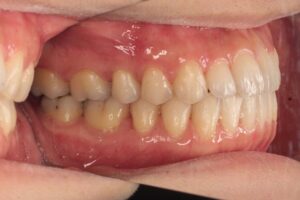

奥歯の咬み合わせは上顎歯列に対して下顎歯列が若干前方位にありました(下顎前突傾向)。また、上顎両側側切歯が若干小さめでした(上下顎前歯部の大きさの不調和)。

治療中、奥歯の咬み合わせの前後関係を補正するために下顎前歯から上顎臼歯にかけて顎間ゴムを水平的に使用しました(Ⅲ級ゴム)。治療前側面写真と治療後側面写真を比較すると、治療後の方が犬歯~小臼歯にかけてより緊密に咬合していることがわかります。